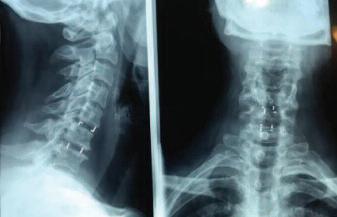

ενδοεγκεφαλικών αγγείων και νόσος των σπονδυλικών αρτηριών Στην περίπτωση ισχαιμικού εγκεφαλικού επεισοδίου που βρεθεί στένωση της καρωτίδας μεγαλύτερη του 70% ή και 50-69% στην ίδια πλευρά με το ημισφαίριο του εγκεφάλου που υπέστη το ισχαιμικό εγκεφαλικό (συμπτωματική καρωτιδική νόσος) πρέπει να δίνονται αντιαιμοπεταλιακά φάρμακα (ασπιρίνη και κλοπιδογρέλη) και υψηλές δόσεις στατινών (φαρμάκων που ελαττώνουν

Αθηρωματική πλάκα

της έσω καρωτίδας

που προκαλούσε

στένωση 80% μετά

10 ημέρες από

εγκεφαλικό ισχαιμικό

επεισόδιο

Διακρίνονται

εξελκώσεις στην

επιφάνεια της πλάκας

και διάχυτη

αιμορραγία (Συμπτωματική

αθηρωματική πλάκα)

την χοληστερίνη) και εφόσον ο ασθενής είναι νευρολογικά σταθερός να πραγματοποιηθεί μέσα στις πρώτες 14 ημέρες επέμβαση για την αφαίρεση της αθηρωματικής πλάκας στην έσω καρωτίδα (χειρουργική

Τοποθέτηση

στέντ στην κοινή και έσω καρωτίδα

Χειρουργική ενδαρτηριεκτομή της έσω καρωτίδας (Α)

και σύγκλειση της αρτηρίας με εμβάλωμα (Β)